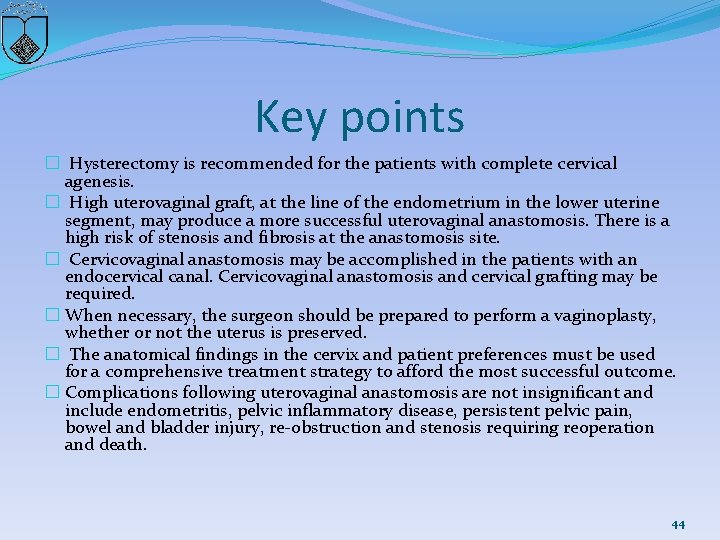

Key points � Hysterectomy is recommended for the patients with complete cervical agenesis. � High uterovaginal graft, at the line of the endometrium in the lower uterine segment, may produce a more successful uterovaginal anastomosis. There is a high risk of stenosis and fibrosis at the anastomosis site. � Cervicovaginal anastomosis may be accomplished in the patients with an endocervical canal. Cervicovaginal anastomosis and cervical grafting may be required. � When necessary, the surgeon should be prepared to perform a vaginoplasty, whether or not the uterus is preserved. � The anatomical findings in the cervix and patient preferences must be used for a comprehensive treatment strategy to afford the most successful outcome. � Complications following uterovaginal anastomosis are not insignificant and include endometritis, pelvic inflammatory disease, persistent pelvic pain, bowel and bladder injury, re-obstruction and stenosis requiring reoperation and death. 44